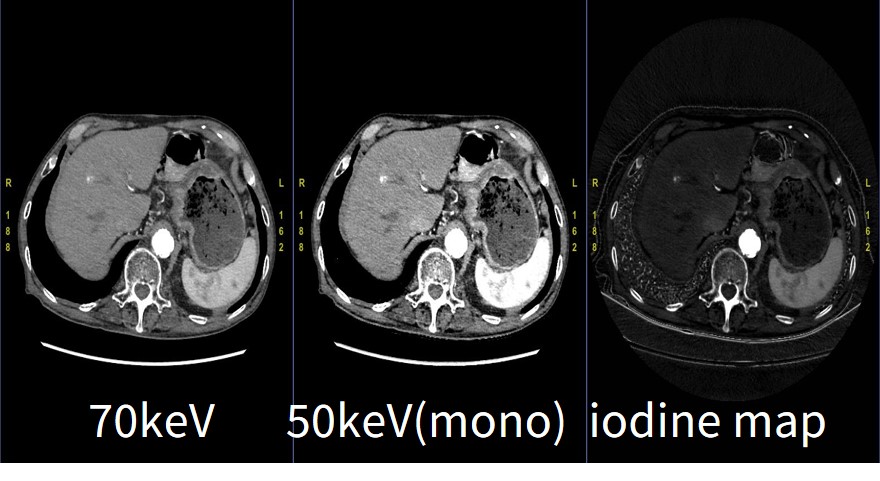

当院では肝胆膵におけるダイナミック検査は全例GSIによるDual Energy撮影を行っている。特に胆膵の腫瘍はコントラストに乏しいことがあるため、Monochromatic imageにおける低keV画像による読影は有用である。(図5)のように乏血性膵がんは低keV画像を用いることにより、腫瘍領域や脈管への浸潤が明瞭となる。

実際のGSI画像読影については読影医がAW Serverにて実施しており、当院ではGSIで撮影した際には全例1.25mmのGSIデータファイルをAW serverへ自動転送している。当院でのGSI画像読影では50keV画像とIodine mapを診る頻度が高く、AW ServerでのGSI画像専用の画像表示レイアウトを作成することで読影医がワンクリックでストレスなく読影できる環境を整えている。(図6)

RevolutionCT_Sasebo05.jpg

図5. GSIによる膵がんの臨床画像

(左:70keV,右:50keV)

RevolutionCT_Sasebo06.jpg

図6. 読影医のAWレイアウト(例)